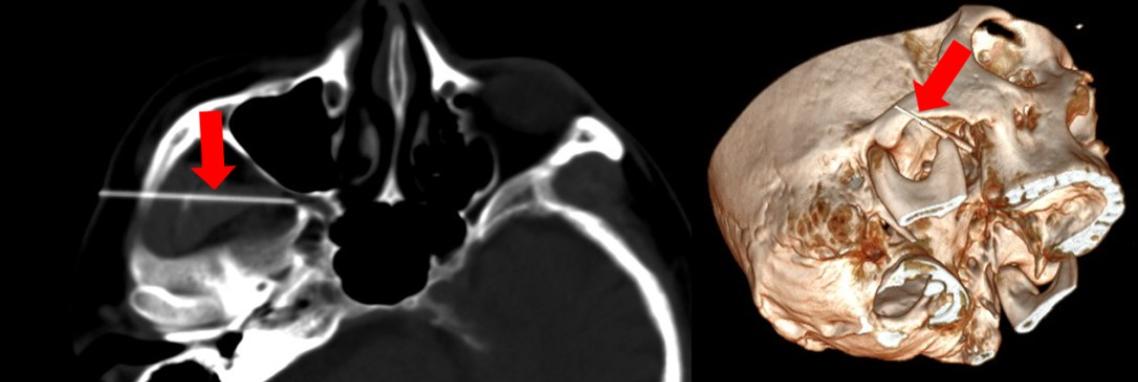

三叉神經痛的微創治療,如神經阻斷或射頻熱凝術,需將細針精準置入顱底神經孔(圓孔、卵圓孔),才能有效破壞病變神經傳導。

藉由這種融合影像,醫師能在畫面上直接標示目標神經孔(例如圓孔、卵圓孔),讓針尖得以沿著最佳、安全的路徑前進至治療位置。